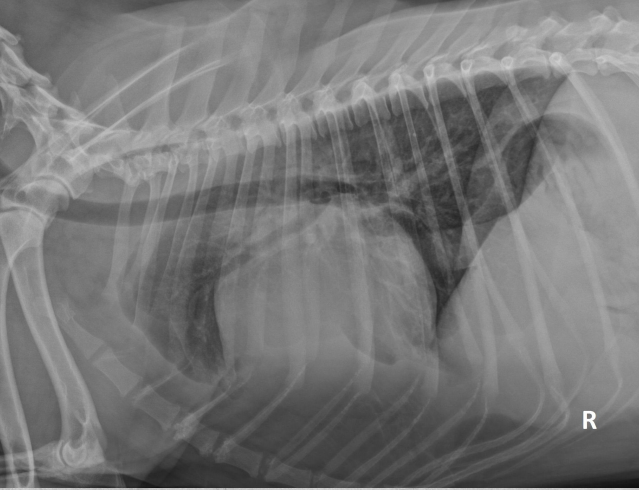

● 12 yo dog

● Coughing for 2 months

alveolar pattern caudodorsally (black tree visible)

fat in ventral thorax

cardiac silhouette lifted and rounded, maybe free fluid

on VD: mass effect